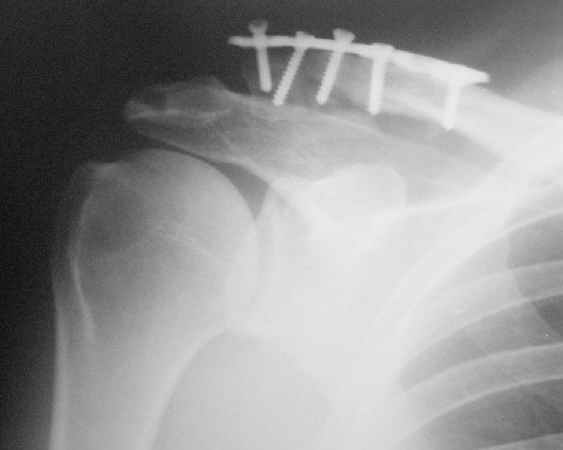

Прошел месяц после остеосинтеза ключицы.

Жалоб больной не предъявляет, работает (предприниматель). Движения в плечевом суставе практически восстановлены. На контрольной R-гр.-положение отломков не изменилось, миграция дистального винта. Следующий осмотр- через месяц.

Перелом обречен на несрастание, сначала мигрирует один винт, после -другой, затем может наступить стресс-перелом пластины. Такой дистальный перелом , если оперировать АО пластиной надо обязательно сочетать с фиксаций АКС, те пластиной блокировать, тогда синтез будет стабильным. Радоваться большому объему движений не стоит, тк при ложном суставе ключицы объем велик, а силы в руке не хватает. Трудно ,но надо решаться на реостеосинтез.